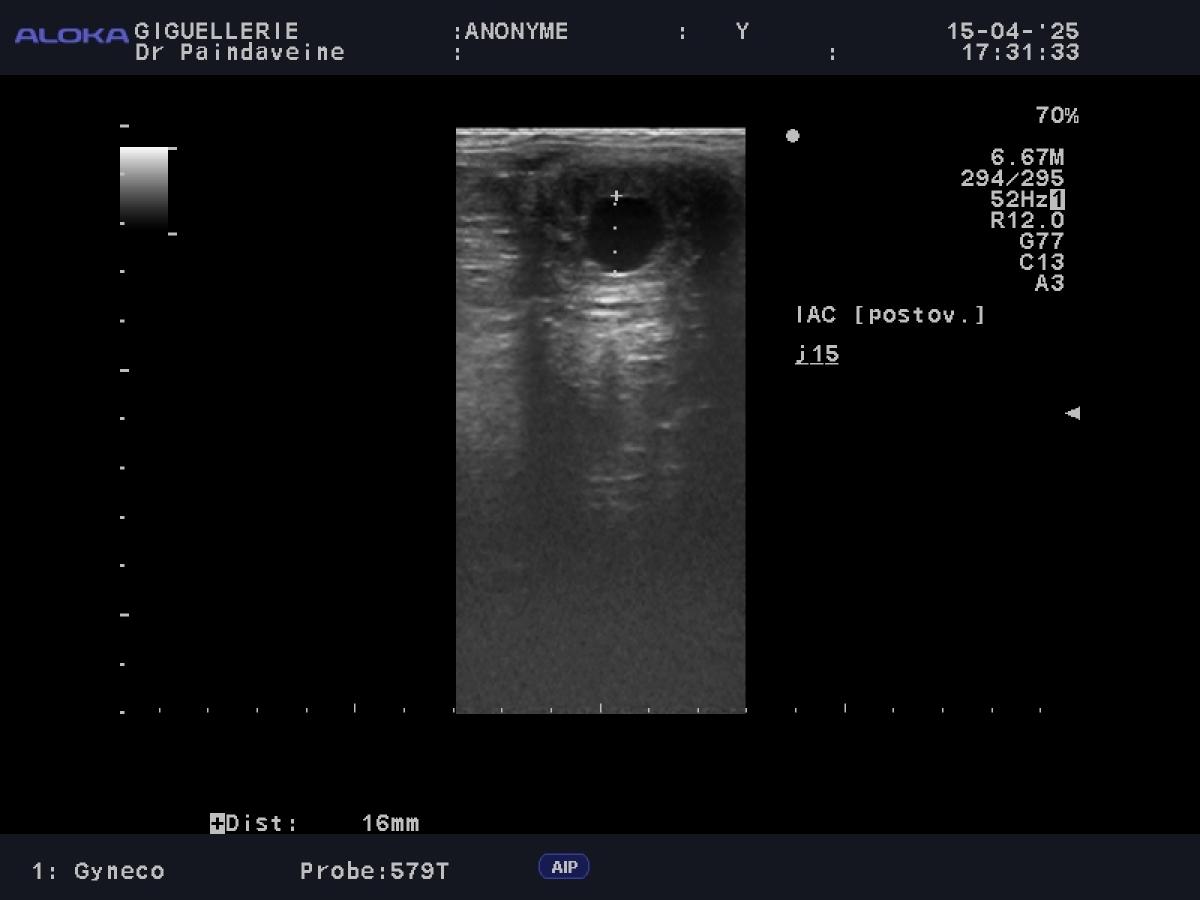

- Ovaries: Monitoring of follicular dynamics to predict ovulation and detect any functional anomalies (persistent corpus luteum, cysts).

- Uterus: Assessment of uterine tone and environment. We pay particular attention to the absence of excessive post-ovulatory edema or endometritis, which are major factors in early failures.

While insemination with fresh or chilled semen offers some flexibility, the use of frozen semen (AI) requires surgical precision. Since the survival of cryopreserved spermatozoa is reduced, monitoring becomes intensive to guarantee semen deposition as close to ovulation as possible.